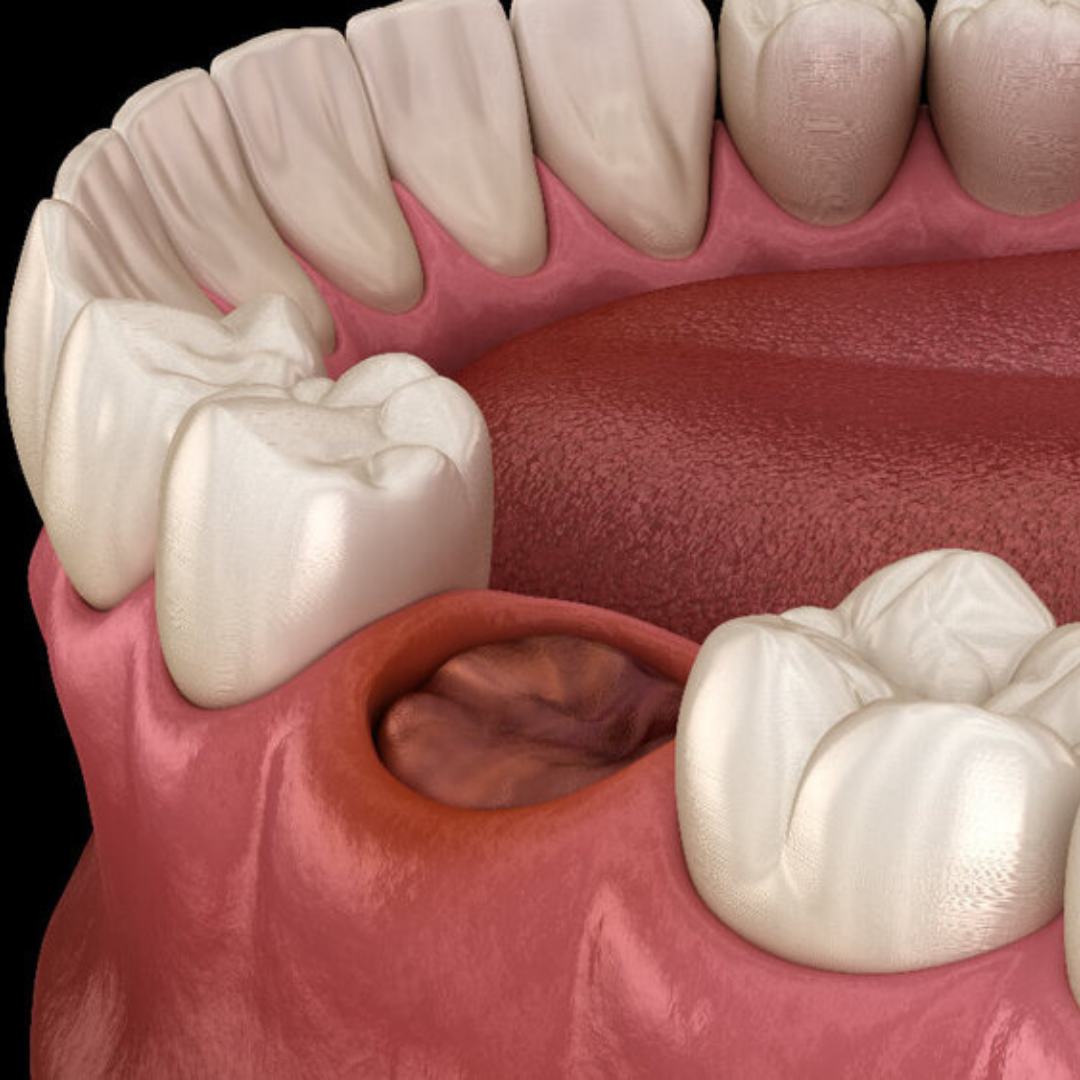

What is a Dry Socket?

After a tooth extraction, especially for wisdom teeth, a blood clot should form in the socket. This clot protects the bone and nerves underneath. If this clot is lost or dissolves too soon in the first 24 hours, it can expose the bone. This can lead to a dry socket, which is a dental emergency. A dry socket causes severe pain and needs urgent care.

- Empty-looking socket where the tooth was removed

- Visible bone in the extraction site